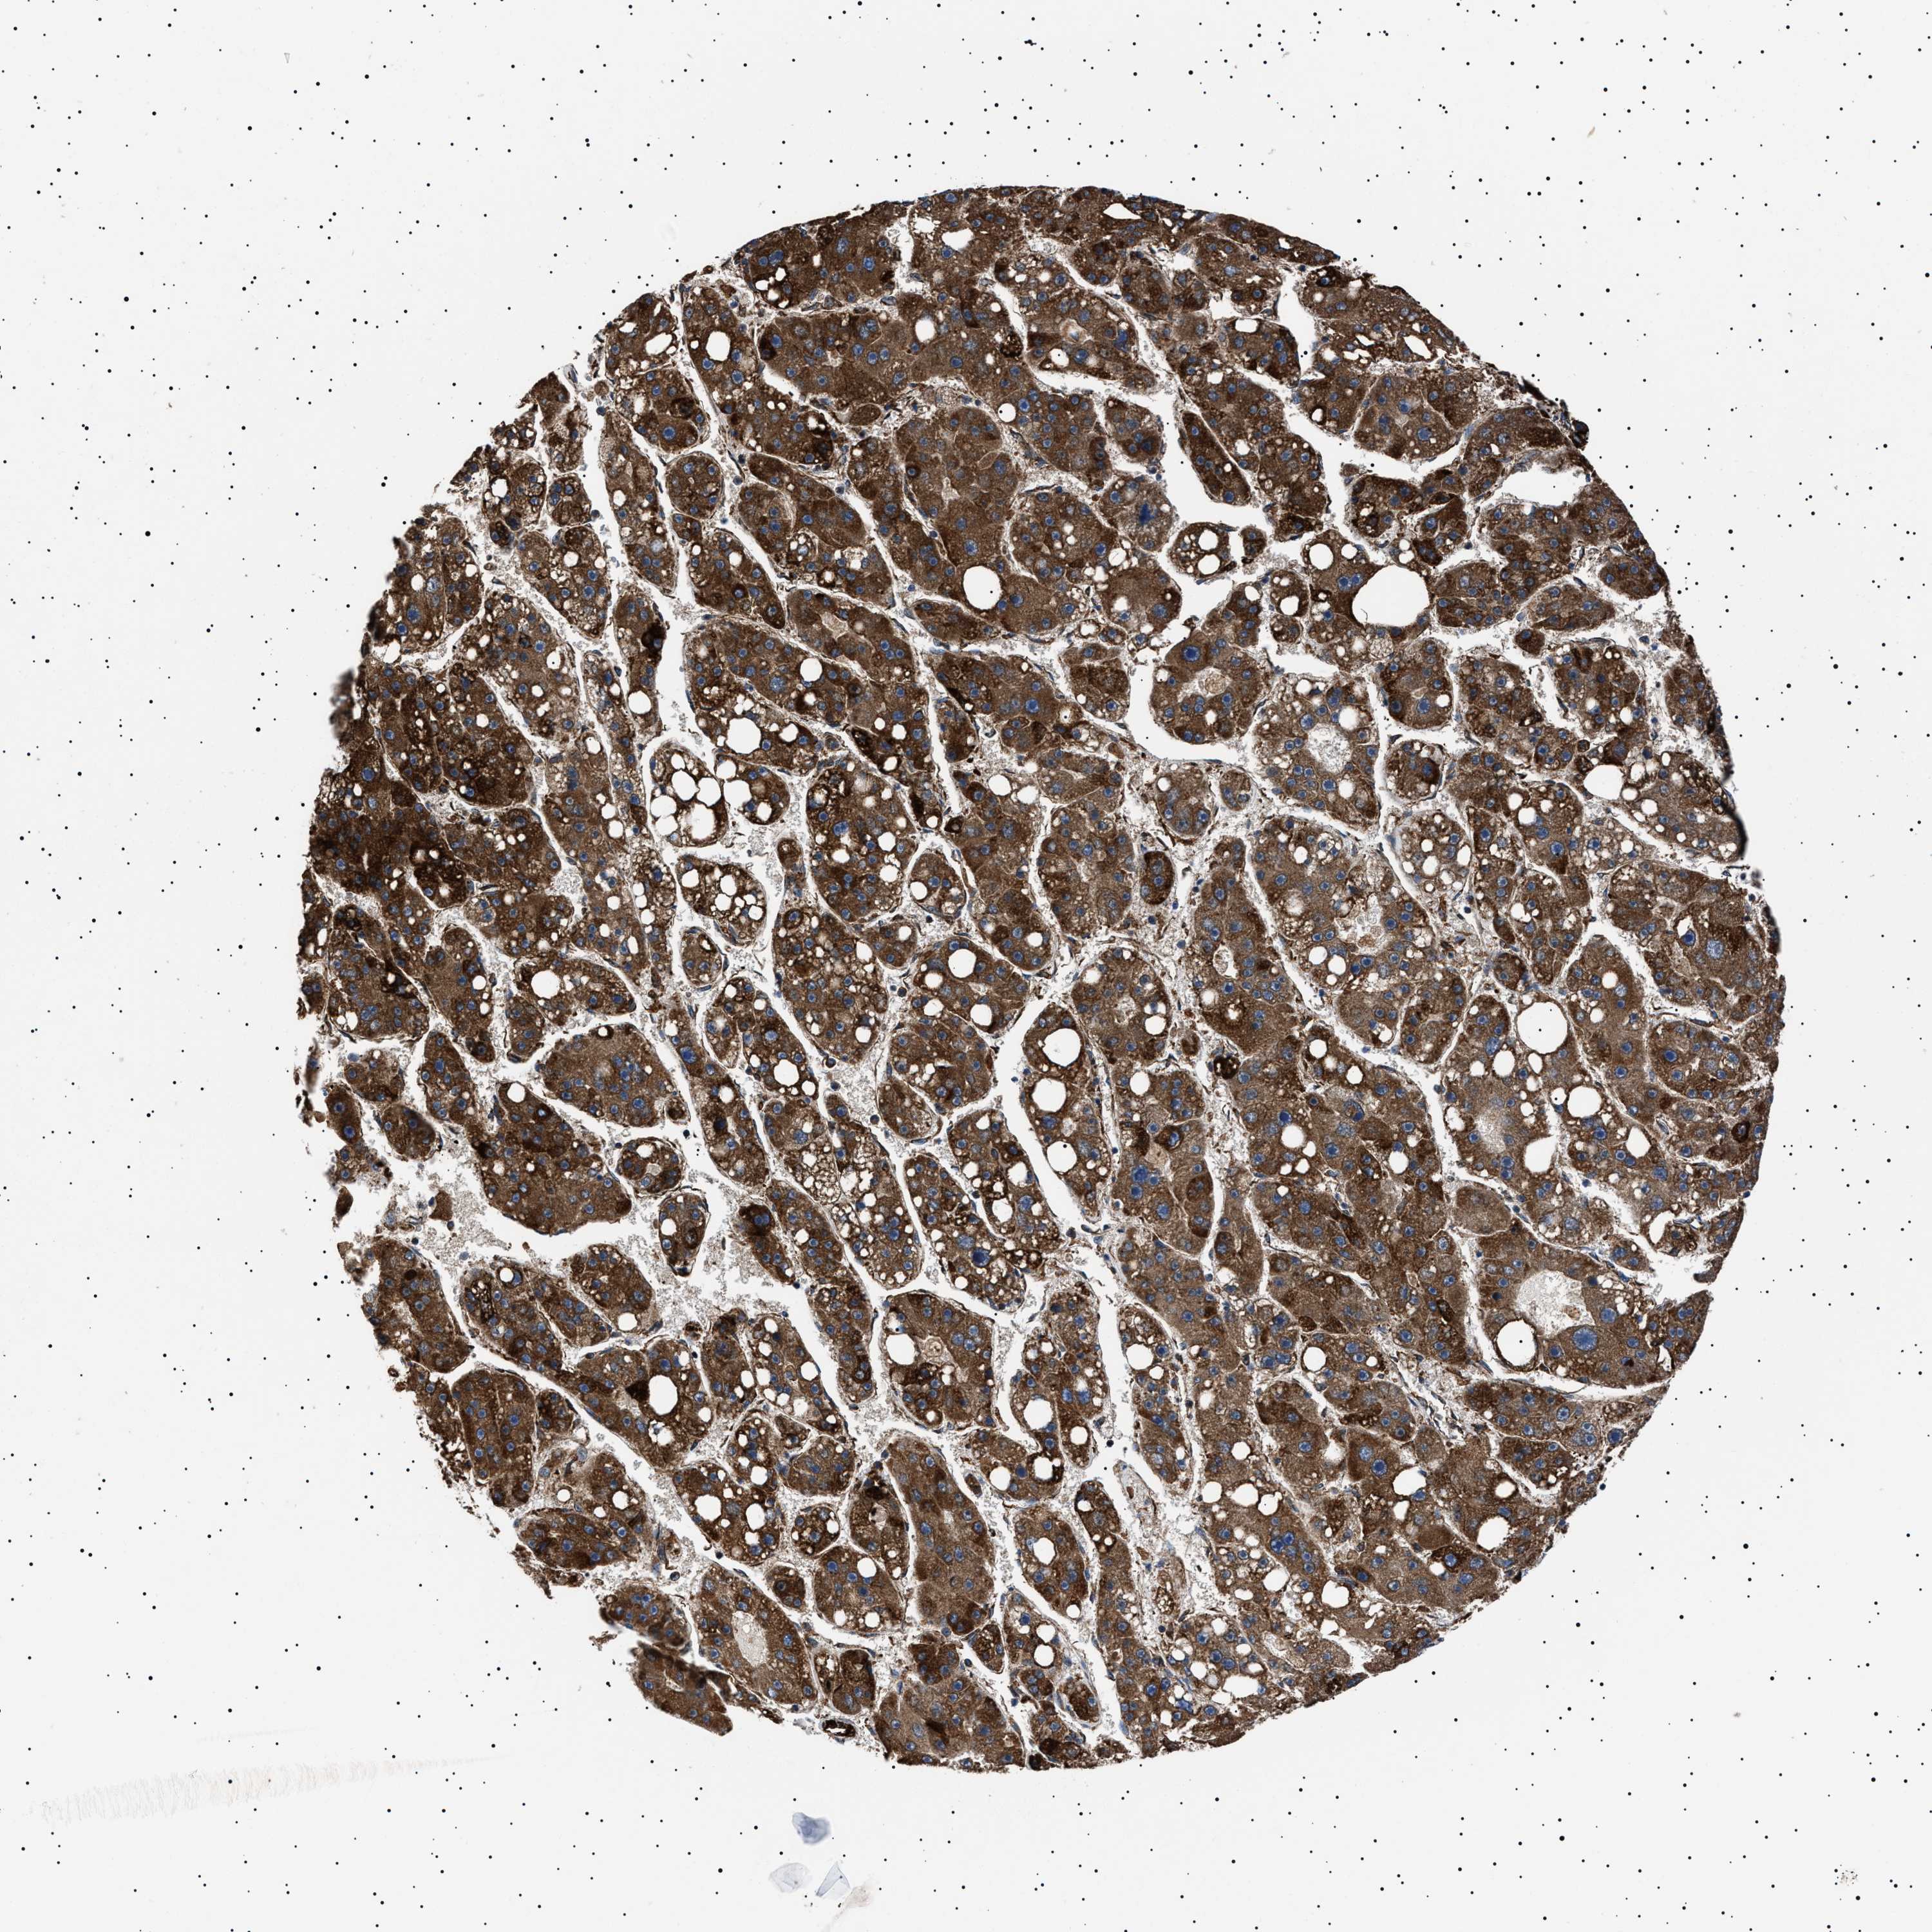

LIVER CANCER - Protein expressioni

A mouse-over function shows sample information and annotation data. Click on an image to view it in a full screen mode. Samples can be filtered based on level of antibody staining by selecting one or several of the following categories: high, medium, low and not detected. The assay and annotation is described here.

Note that samples used for immunohistochemistry by the Human Protein Atlas do not correspond to samples in the TCGA dataset.

Antibody stainingi

Antibody staining in the annotated cell types in the current human tissue is reported as not detected, low, medium, or high, based on conventional immunohistochemistry profiling in selected tissues. This score is based on the combination of the staining intensity and fraction of stained cells.

Each image is clickable and will lead to virtual microscopy that enables deeper exploration of all samples and also displays staining intensity scores, fraction scores and subcellular localization as well as patient and tissue information for each sample.

Antibody HPA001915

Antibody HPA021542

Staining

High

Medium

Low

Not detected

Intensity

Strong

Moderate

Weak

Negative

Quantity

>75%

75%-25%

<25%

None

Location

Nuclear

Cytoplasmic/membranous

Cytoplasmic/membranous,nuclear

Cholangiocarcinoma

Carcinoma, Hepatocellular, NOS